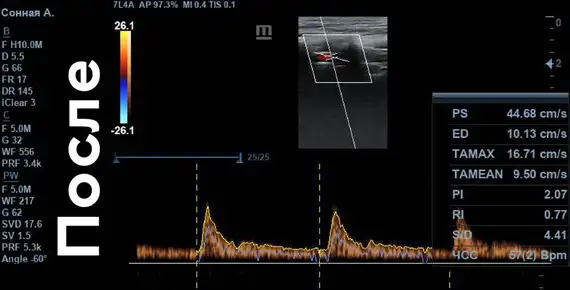

Скорость кровотока «ПОСЛЕ»